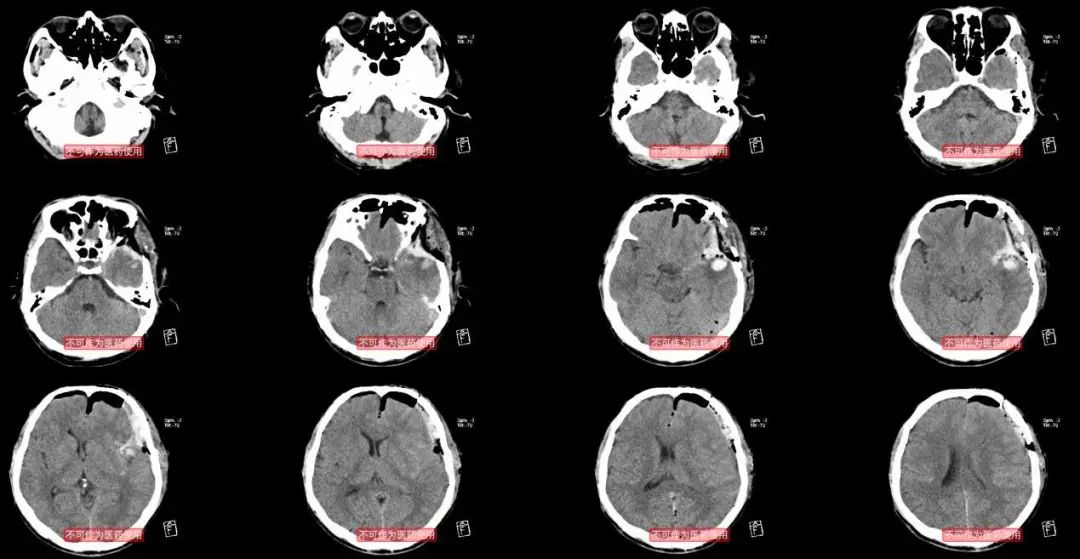

由于中华医学会神经外科年会在兰州举行,我9月9日还有大会发言,准备了9月8日去兰州的航班。所以术后当日晚上复查头颅CT:有少量渗血,不需要再次手术。

术后当日的CT